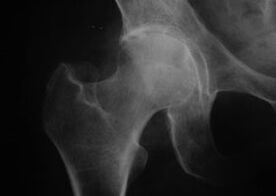

Coxatrosis, artrosis de la articulación de la cadera.

Con esta enfermedad, se observa el cuadro clínico de artrosis.

El primer síntoma de la coxartrosis es el malestar en la articulación de la cadera después de la actividad física.

Con la coxartrosis progresiva, aparecen aumento del dolor, rigidez y movimiento limitado.

Los pacientes con una forma grave de coxartrosis liberan la extremidad afectada, evitan pisarla y, mientras están quietos, eligen una posición en la que se sienta menos dolor.